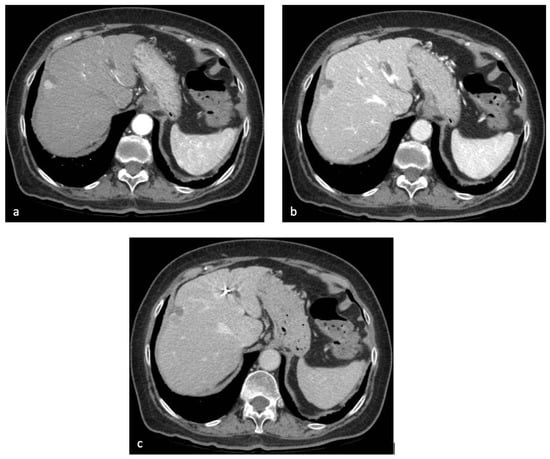

Whereas the portal-venous phase is sufficient for the detection of hypovascular liver metastases, the late arterial and delayed phases are most important for the evaluation of hypervascular tumors including HCC (Figure 2).

Contrast-enhanced CT of the upper abdomen in the patient discussed in Figure 1. After administration of iodinated contrast agent, the subcapsular lesion showed arterial hyperenhancement (a), with progressive wash-out in the portal-venous (b) and delayed (c) phase.

The typical hallmark diagnostic feature of HCC is the combination of non-rim APHE on the late arterial phase and non-peripheral wash-out appearance on the portal-venous and/or delayed phases, thereby reflecting the peculiar vascular derangements induced by hepatocarcinogenesis [49].